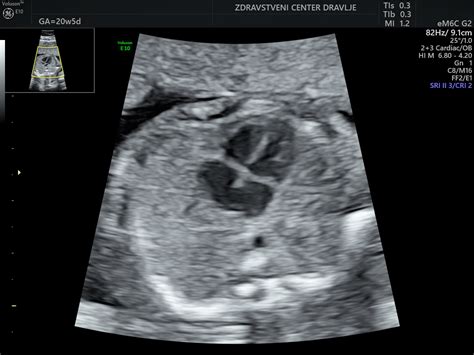

Pomembna sprememba v tem obdobju je premik testisov pri fantkih iz trebuha v mošnjo. Na ultrazvoku je mošnja v tej fazi pogosto videti povečana zaradi zadrževanja tekočine. Zadrževanje tekočine je sicer značilno za nosečnost in se odraža v oteklih okončinah, kar je posledica povečanega volumna krvi.